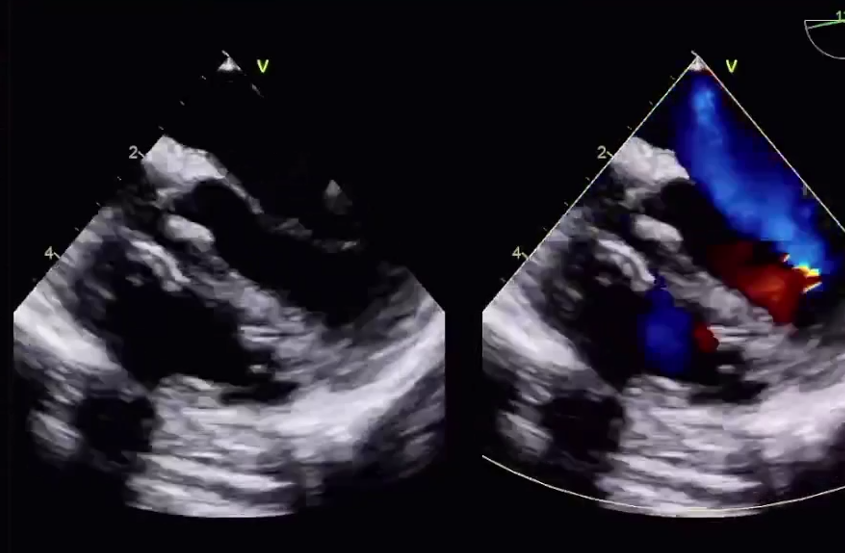

结合评估结果和患者及家属意愿,术者团队使用了我国自主研发的Bio-Lefort生物可降解左心耳封堵器,行射频消融+左心耳封堵“一站式”手术。射频消融完成后实施左心耳封堵,封堵器送入后,位置、锚定情况良好,牵拉试验稳定,符合释放原则,遂完全释放封堵器,术后造影示无残余分流,复查超声证实封堵器位置良好,封堵效果理想,手术成功!

▲ 术后超声 ▲